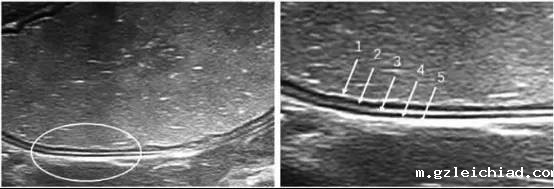

1.高回声(黏膜上皮层);2.低回声(黏膜深层);3.高回声(黏膜下层);4.低回声(固有肌层);5.高回声(浆膜层)